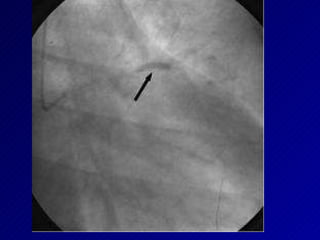

Apertura arterial y sobrevivencia GUSTO-1:  estudio angiográfico evidencia  reducción de la mortalidad en función de apertura temprana de la arte ria. Reperfusión durante 6-12 hs resulta en reducción mortalidad. Cuantificación flujo epicardico propuesto por el estudio TIMI: Grado 0:  No perfusión Grado 1:  Penetración contraste  en el trombo  sin perfusión distal Grado 2:  Perfusión parcial con lento flujo distal Grado 3:  Flujo completo normal distal a la circulación coronaria

Apertura arterial ysobrevivencia GUSTO-1: estudio angiográfico evidencia reducción de la mortalidad en función de apertura temprana de la arte ria. Reperfusión durante 6-12 hs resulta en reducción mortalidad. Cuantificación flujo epicardico propuesto por el estudio TIMI: Grado 0: No perfusión Grado 1: Penetración contraste en el trombo sin perfusión distal Grado 2: Perfusión parcial con lento flujo distal Grado 3: Flujo completo normal distal a la circulación coronaria